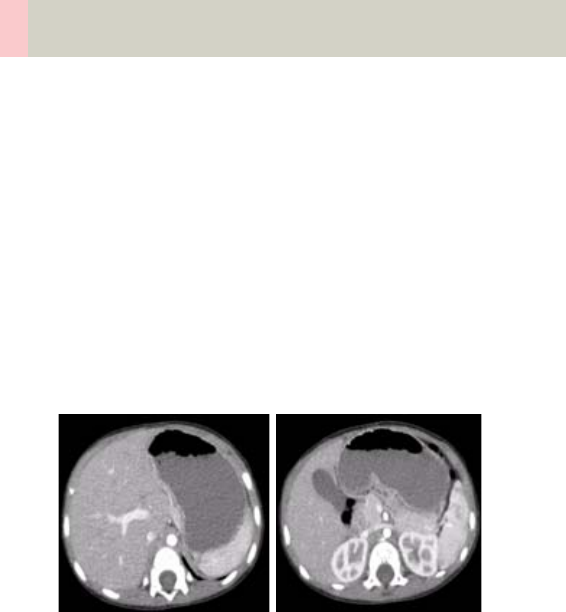

Abdomen 262

•Overview 262

- General Hints 264

- Body Kernels 265

•Scan Protocols 266

- AbdomenRoutine/

AbdomenRoutine06s 266

- AbdomenCombi/

AbdomenCombi06s 270